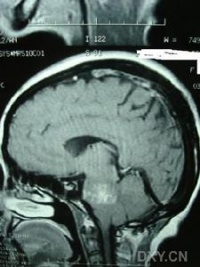

(2)CT及MRI扫描:CT表现为瘤体呈等密度或低密度,少数呈高密度影像。肿瘤多为圆形或不规则形,位于内听道口区,增强效应明显。MRIT1加权像上呈略低或等信号,在T2加权像上呈高信号。第四脑室受压变形,脑干及小脑亦变形移位。注射造影剂后瘤实质部分明显均一强化,囊变区不强化。

(3)CT及MRI检查:目前听神经鞘瘤诊断的标准是Gd-DTDA增强的MRI,特别是当肿瘤很小(<1cm)或在内听道内,CT扫描阴性又高度怀疑肿瘤存在时应该进行GD-DTPA增强的MRI。CT与MRI两种检查有相辅相成的作用,如CT发现有病侧内听道扩大时,增强CT可发现肿瘤对于估计中颅窝入路时颞骨的气化程度及高颈静脉球与后半规管及底的距离有帮助。如果病人已作了CT而肿瘤较大,MRI可提供对脑干压迫的范围Ⅳ脑室是否通畅脑积水、是否存在的情况对可疑听神经鞘瘤或CT检查难于确定时,全序列的MRI可做出鉴别诊断。但也要注意Gd-DTPA的可能假阳性,这与内听道内神经的炎症或蛛网膜炎有关;任何小的接近底部的增强病变应该在六月后作MRI复查,以评估其生长情况。